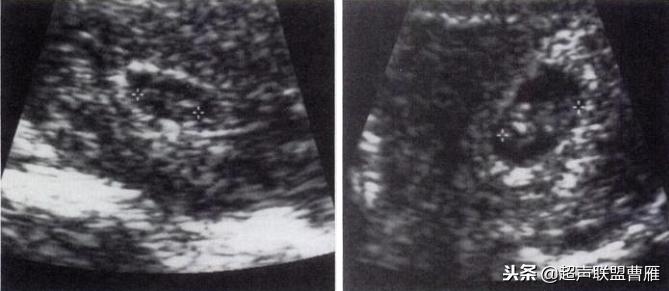

一个孕囊有两个卵黄囊,单卵双胎。

两个孕囊各有一个卵黄囊,双卵双胎,HCG应该更高。

正常早孕卵黄囊声像图

早孕 胚芽 卵黄囊

5周+ 、6周+ 声像图

孕7周左右(胚芽11mm 卵黄囊)

胎芽 卵黄囊 心管搏动信号

宫内早孕 (7周左右)